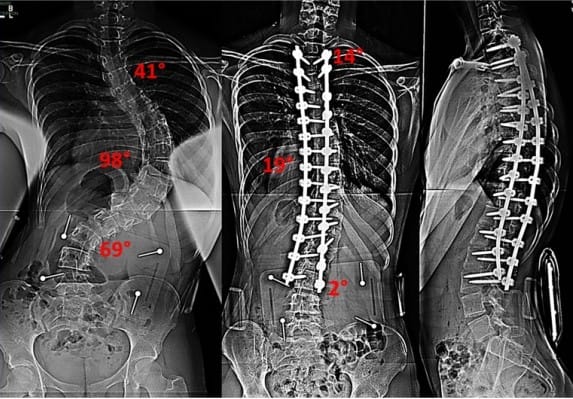

RENTGEN

Na rentgenskem posnetku merimo skolioze z meritvijo po Cobbu. Ta kljub temu, da ne opisuje 3D geometrije hrbtenice, še vedno velja za standardno klinično uporabno metodo. Pri določanju krivine najprej določimo zgornje in spodnje vretence, ki še pripadata tej ravnini. Nato potegnemo črti po zgornji ploskvi zgornjega in spodnji ploskvi spodnjega vretenca in pravokotnici na tej daljici. Ostri kot med tem dvema črtama imenujemo Cobbov kot (Persall, D. J., Reid, J. G. & Hedden, M. D. (1992). Comparison of Three Nonincasive Methods for Measuring Scoliosis. Ohys Ther, 72(9), 648–657).